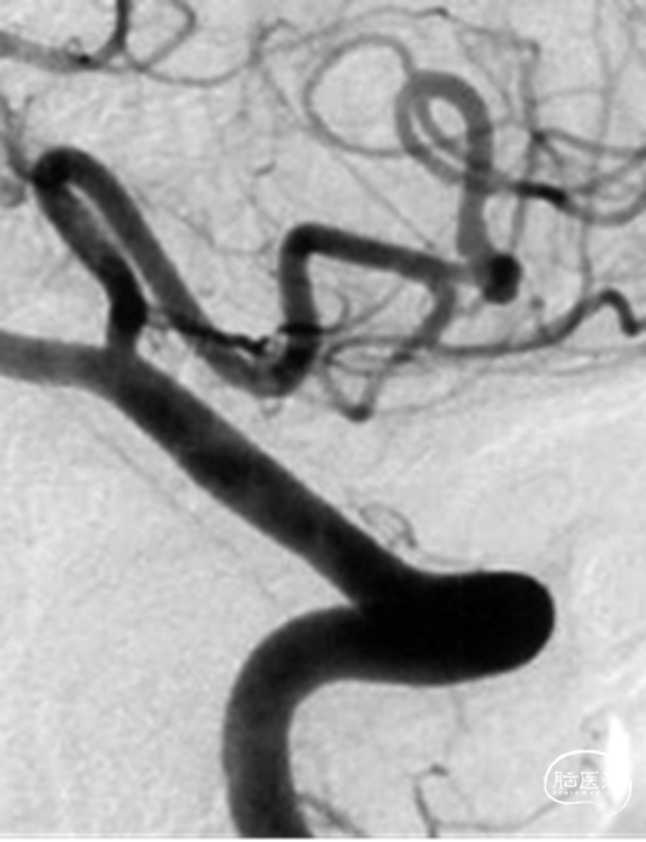

入院急诊DSA提示右侧小脑后下动脉远端动脉瘤,动脉瘤位于PICA蚓部分支

二维及三维重建提示动脉瘤形态不规则,可见瘤壁存在小泡凸起,瘤颈宽3.6mm,瘤高2.0mm,瘤体最大径2.5mm,未见血管明显痉挛